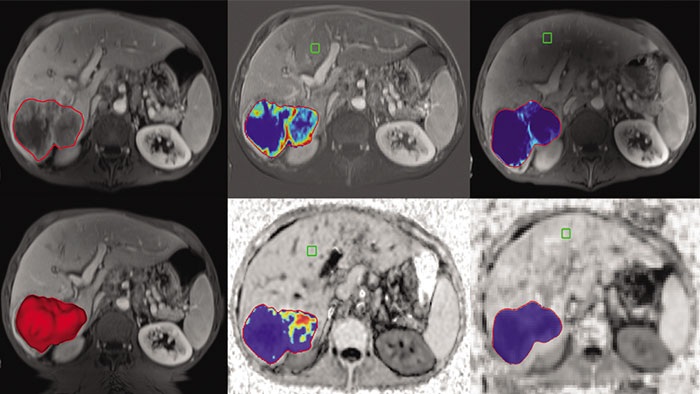

Semi-automatic tumor quantification

This semi-automated 3D (Volumetric) tumor response assessment tool, based on EASL (European Association for the Study of the Liver) criteria incorporates functional information from contrast-enhanced scans.

Benefits